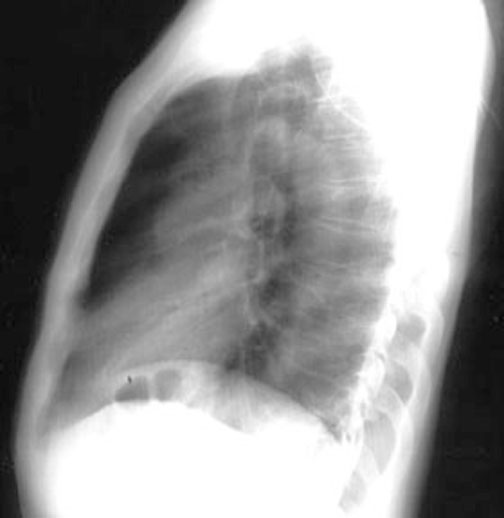

Case 38

Lateral

Labeled Image